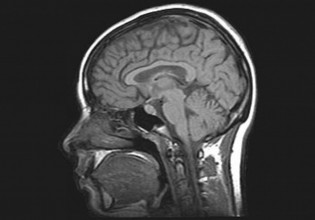

Να σημειωθεί ότι έχουν περάσει την κόκκινη γραμμή οι συνθήκες νοσηλείας των πασχόντων με κοροναϊό στα νοσοκομεία της Αχαΐας. Ιδιαίτερα αυτό αφορά τους διασωληνωμένους καθώς οι ΜΕΘ εμφανίζουν πληρότητα 100% και χθες στο ΠΓΝΠ νοσηλεύονταν 11 διασωληνωμένοι στις κοινές κλινικές κοροναϊού.

«Χθες, 11 ασθενείς διασωληνωμένοι νοσηλεύονταν σε κοινές Κλινικές Κορονοϊού στο Πανεπιστημιακό Νοσοκομείο. Πρόκειται για άκρως απάνθρωπη κατάσταση. Κι αυτή δυστυχώς νομιμοποιείται από τα λεγόμενα του πρωθυπουργού στη Βουλή. Λύσεις υπάρχουν, γιατί δεν υιοθετούνται από τη διοίκηση της υγείας; Ποιος θα λογοδοτήσει που συνάνθρωποί μας στερούνται τις δέουσες συνθήκες νοσηλείας;» Ο κ. Ζιαζιάς καλεί τους αρμοδίους να λάβουν άμεσα μέτρα και να εξασφαλίσουν στους ασθενείς αυτό που τους αρμόζει.